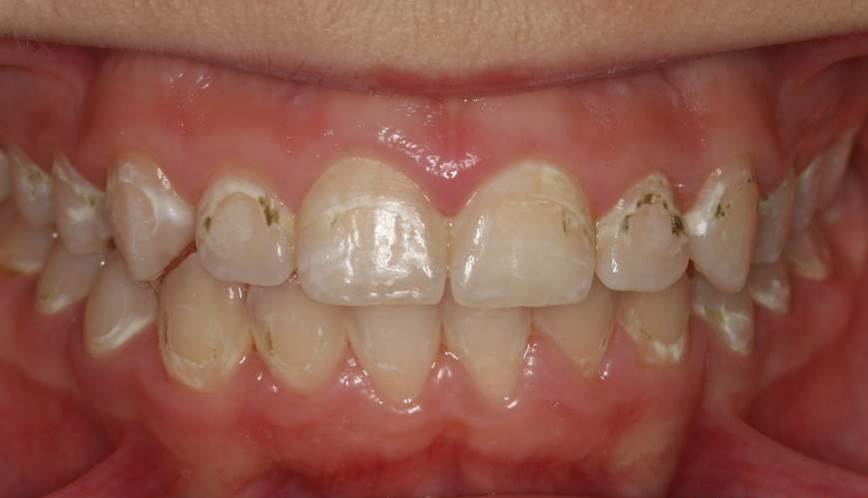

1、治疗前。正畸后患者